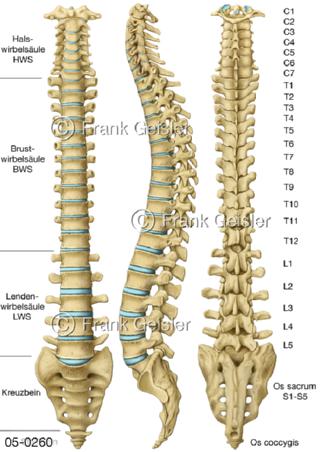

Bildergalerie Skelettsystem

Bilder zum Skelettsystem zeigen die Stützstruktur des menschlichen Körpers, die Knochen, eine besonders harte Form des Bindegewebes und Stützgewebes, welche das menschliche Skelett bildet, die Knochen des Stammes, der Extremitäten sowie der Gelenke